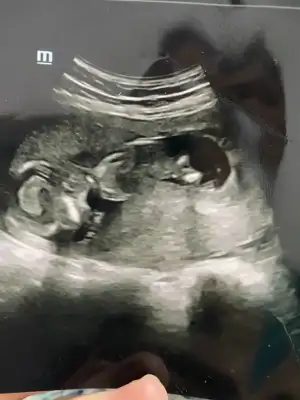

Cnm daha önce atmıştım arkadaşımın Buda 13+ 2 yorularmısın Ikra meyra Ikra meyra

Eklentiler

• 6542ED3F-0D56-43B6-AECA-3BBC0FD83B62.webp

6542ED3F-0D56-43B6-AECA-3BBC0FD83B62.webp

20,7 KB · Görüntüleme: 104